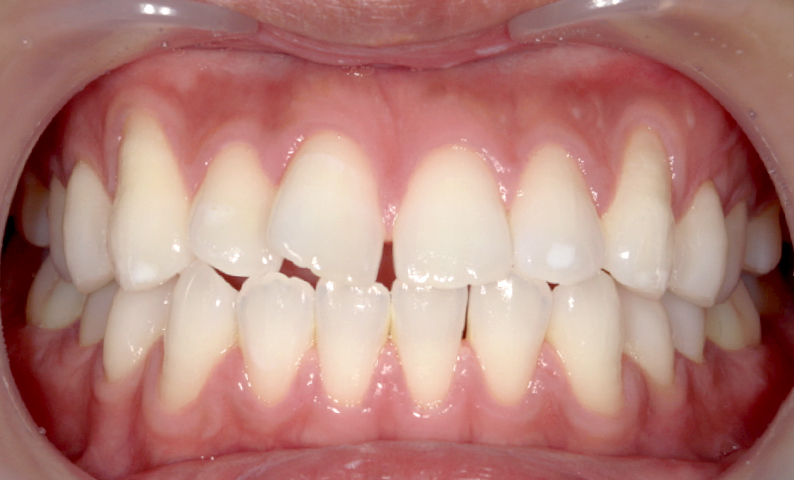

| 治療前 | 治療後 |

|---|---|

|